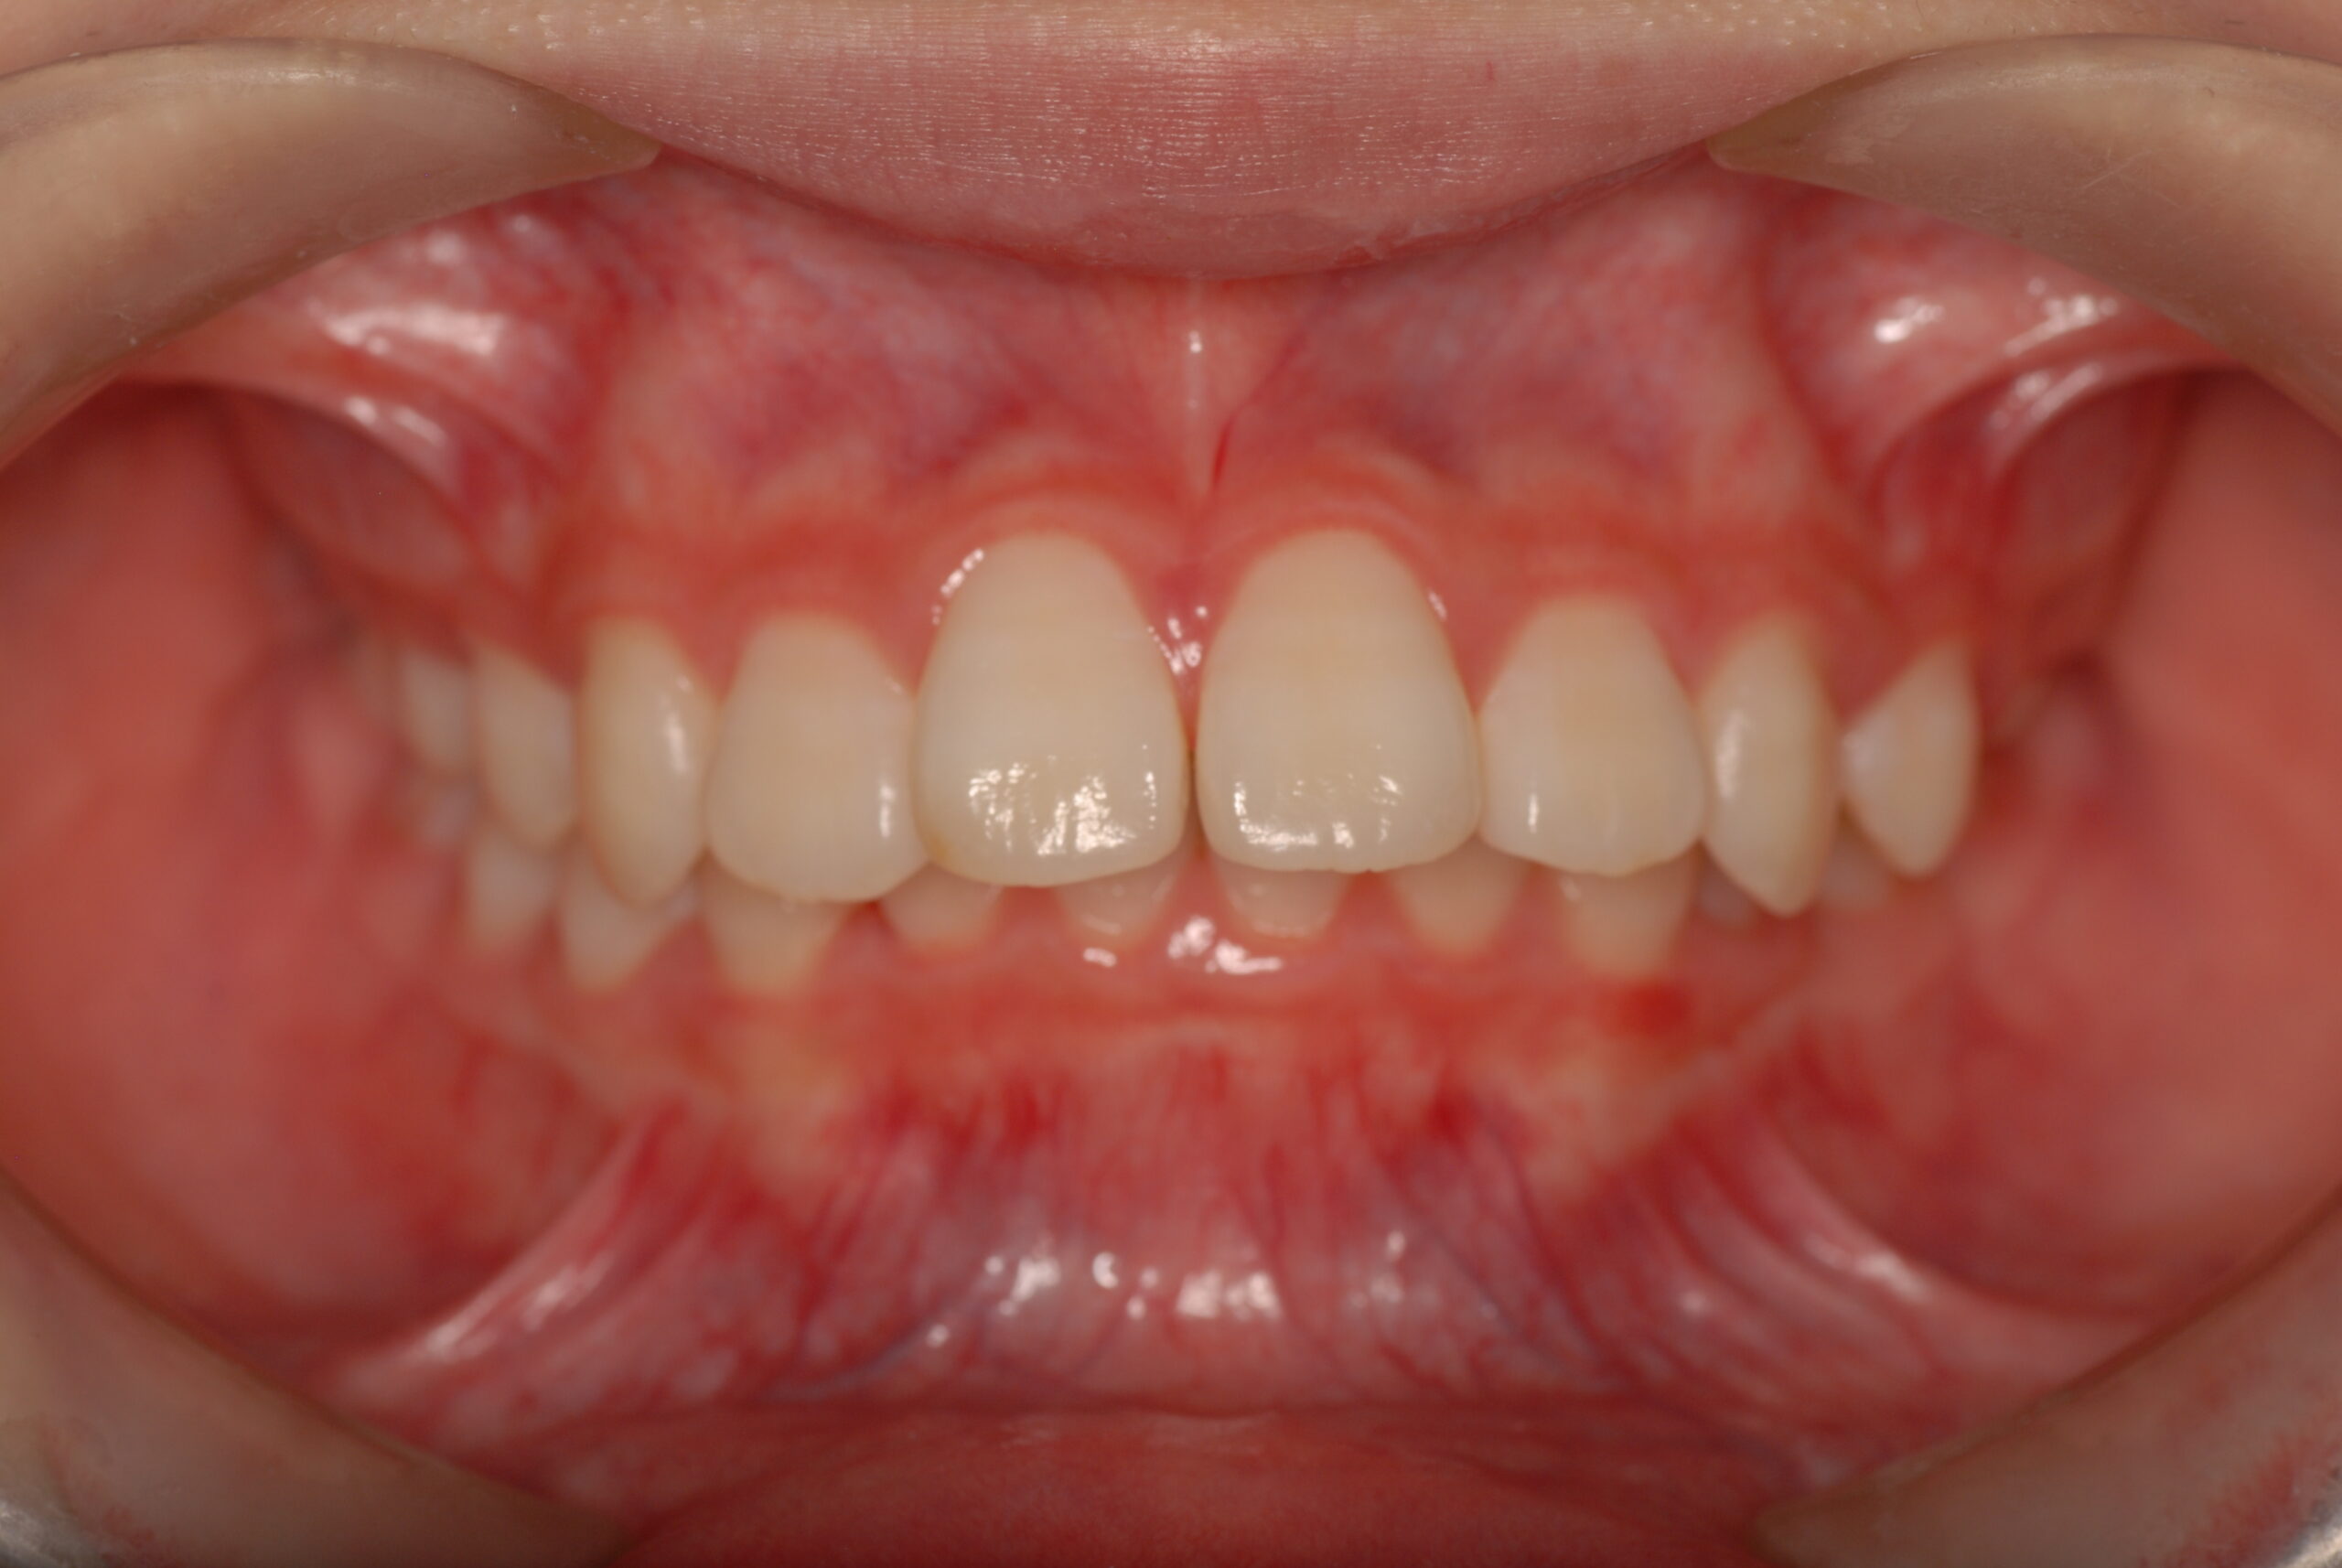

Before

- 主訴

- 上の前歯が出ている。

- 診断名、治療内容

- 上顎前突、叢生。 上下顎第一小臼歯を抜歯し、抜歯空隙を利用し、顎外固定装置としてヘッドギヤを併用しながら、上顎前歯を可及的に後退させる。